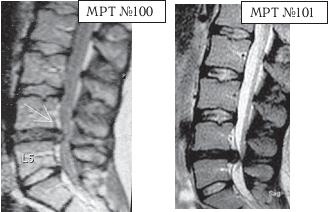

На МРТ № 100 наблюдается грыжа межпозвонкового диска LIV-LV Состояние до операции. На МРТ № 101 наблюдается послеоперационный рецидив грыжи межпозвонкового диска в сегменте LIV-LV.

Несколько лет назад у данного парня диагностировали грыжу межпозвонкового диска (МРТ № 100). Врачи сказали, что надо срочно оперироваться, однозначно, иначе будут проблемы как с ногами, так и с органами таза. Естественно, это сообщение вызвало страх у молодого парня, тем более его убедили, что грыжи межпозвонкового диска без операции, то есть консервативно, не лечатся. Парень согласился на операцию. Со слов пациента, практически год после операции он чувствовал себя неплохо, «побаливало иногда, но в пределах терпимого». Состояние было относительно удовлетворительное. Однако позже боли начали усиливаться, перешли на ноги. Ещё один год пациент лечился консервативно. Лежал в неврологическом отделении, затем лечился в санатории. Физических нагрузок после операции не было. То есть, по сути, применялись медикаментозные методы лечения, физиотерапия. Методы вытяжения позвоночника и мануальной терапии не применялись. И всё же, несмотря на такой щадящий подход в лечении, боли возобновились. Сделали повторное МРТ (№ 101), диагностировали рецидив грыжи межпозвонкового диска. Естественно, предложили повторную операцию. На этот раз пациент отказался. Через знакомых узнал о методе вертеброревитологии и обратился ко мне в клинику.